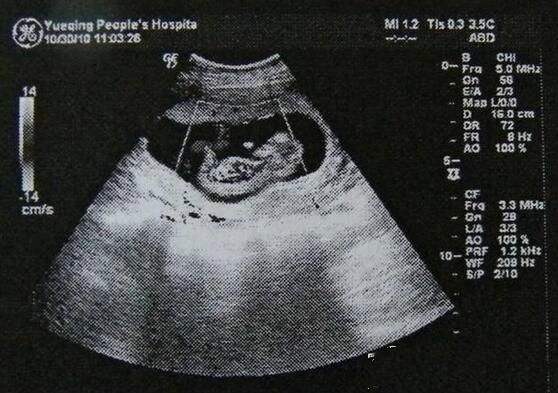

妈妈在怀孕时期做B超非常的重要,怀孕早期做B超可以检查出是否出现了宫外孕的情况,还可以检查出胎芽大小、胎儿的发育情况等。怀孕中期做B超可以检查出孩子的面部。神经系统以及消化系统等众多系统的发育是否正常。怀孕后期做B超尤为重要,可以检查出是否前置胎盘、胎盘的成熟程度等非常多的情况,最终可以决定妈妈们是否应该中止妊娠,因为这对于产前的婴儿健康可以起到非常准确的判断。因此,B超是妈妈们在怀孕期间必须要做的检查,但是B超单上的各种数字,妈妈们却都看不懂,它们都代表着什么呢?还有一些四处听来的关于B超单的说法,它们又是不是正确的呢?下面我们就一起来揭开B超单神秘的面纱吧。

以36周为例,一起来看看B超上数字含义

双顶径指的是婴儿头部两侧之间的最宽长度,在B超上写的是BPD,36周的宝宝的BPD标准长度是90MM,大概是一个苹果的大小,在这个基础上,长或者是短6MM都是属于正常现象,只要在这个范围内,妈妈们就可以不用担心了。宝宝36周时的腹围是在290MM到360MM之间都是标准的,大概是一个葡萄柚的大小,腹围在B超单上写作AC。B超上还会出现股骨长和肱骨长,它们分别是FL和HL,其实指的就是宝宝的大腿和手臂,大腿在63MM到75MM,手臂在57到67MM都是属于正常的,就和雪莲果的大小差不多。而B超单上还会出现一个FL/AC,就是用股骨长除以腹围,这是一种科学的预算术,可以在一定程度上预测宝宝的发育情况,在20%到24%都是正常的,超过了这个范围,就需要妈妈们留心注意了。

最后B超单上还会出现一个羊水指数,这是为了得到更加准确的结果,方便了解胎儿在妈妈羊水中的情况,所以就把妈妈的子宫分为了四个象限,分别测出羊水深度然后相加,得到的结果就是羊水指数,正常范围是在8到24CM之间,羊水过多可能会出现早产的情况,还有可能会造成胎位异常,因此妈妈们一定要注意了。